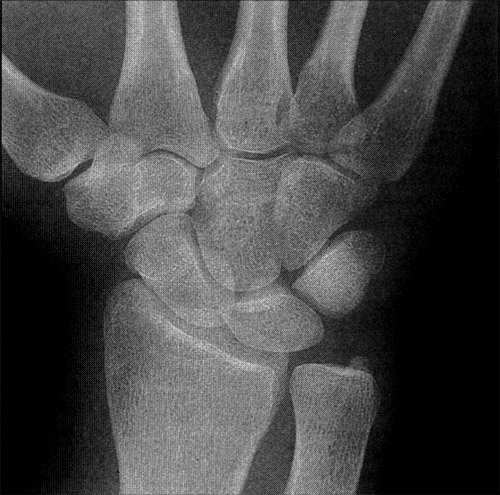

신경통은 신경에의 확실한 외상에 기인될 수 있으며, 수부에서는 손목부위에서 요골신경과 정중신경의 손상시 흔히 발생된다. 그러나 신경의 손상 이외에도 타박상 등 여러 종류의 외상, 골조송증, 당뇨병이나 중금속 중독 등과 관계가 있는 각종의 신경염, 그리고 심하면 특별한 이유 가 없이 발생하는 일도 있어 이러한 질환의 존재 여부가 의심스러울 수도 있다.

통증 부위 관절만의 문제인지 아니면 다른 관절들과의 상호작용이 원활하지 않아 생겨난 문제인지 판별하는 것이 중요하다. 국소관절의 문제라면 해당 관절의 근육과 인대의 작용이 정상인지 검사하여 문제 소견을 없애는 치료를 하면 되고 다른 관절과의 상호작용에 문제가 있는 경우는 다른 관절도 동시에 치료한다. 또한 척추 전반의 문제를 점검하여 문제가 있는 경우 추나 치료를 실시한다.